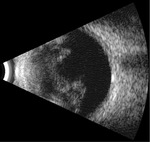

Rycina 6. Odwarstwienie siatkówki oraz wylew krwi do ciała szklistego na skutek niedawno przebytego urazu tępego